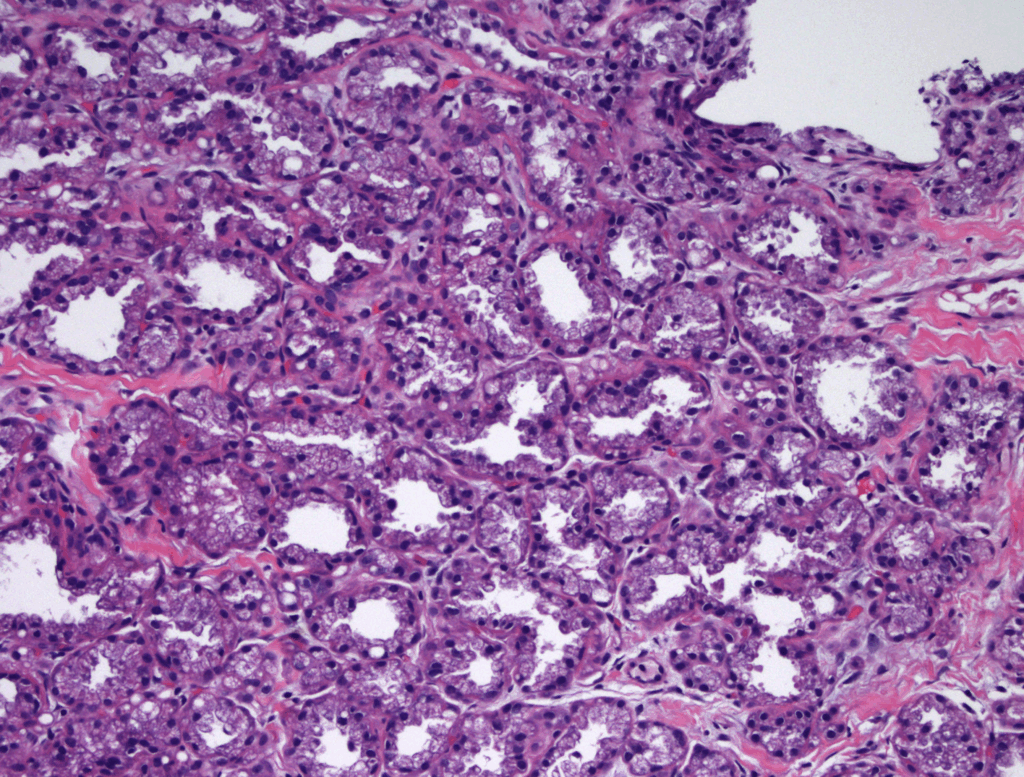

Idiopathic Granulomatous Mastitis (IGM or GM)

Idiopathic granulomatous mastitis (IGM) is an inflammatory disorder affecting the breast of young women in their childbearing years, and can overlap with lactation and pregnancy. It can result in development of painful inflammatory masses, fluid collections, and fistula formation. While breastfeeding from the affected breast in the setting of IGM is safe, many mothers report significant pain and difficulty with latch or milk production.

While some cases of IGM may resolve from a simple mass, many go on to form fluid collections (above and below) that may drain on their own. These are mistakingly called “abscesses.” They are in fact just fluid collections of dead inflammatory cells. Patients need either local treatment with needle drainage of the fluid (NOT large incisions with packing tape, which make inflammation worse) and steroid injection, or oral steroids/anti-inflammatories/immune suppressants.